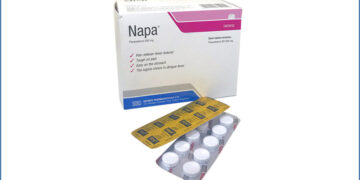

Read moreহার্টবিট ডেস্ক নাপা সিরাপ নয়, ব্রাহ্মণবাড়িয়ায় মায়ের পরকীয়ার জেরে দুই শিশুকে হত্যা করা হয়েছে বলে জানিয়েছে পুলিশ। এ ঘটনায় মা লিমা বেগমকে...

Read moreহার্টবিট ডেস্ক ‘নাপা সিরাপ’ খেয়ে ব্রাহ্মণবাড়িয়ার আশুগঞ্জে দুই শিশুর মৃত্যুর ঘটনায় বেক্সিমকো ফার্মাসিউটিক্যালস লিমিটেডের নাপা সিরাপের একটি ব্যাচ পরীক্ষা-নিরীক্ষা করে...

Read moreহার্টবিট ডেস্ক সারা দেশ থেকে নির্ধারিত ব্যাচের (ব্যাচ নং-৩২১১৩১২১) নাপা সিরাপের নমুনা সংগ্রহের নির্দেশ দিয়েছে সরকার। একই সঙ্গে কারও কাছে...